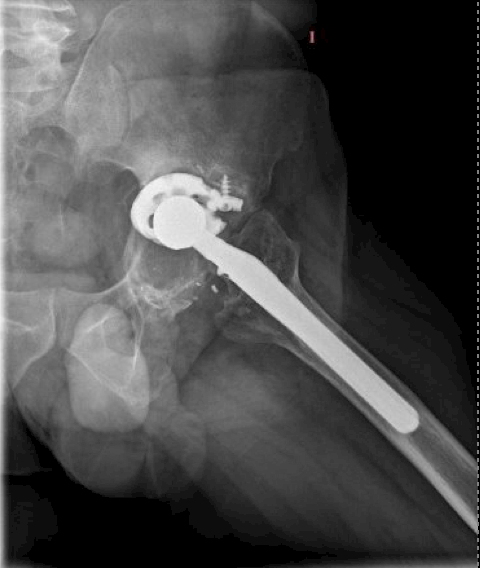

October 2022:

- Age: 48 years

- Reports pain

- Follow-up scheduled for 2023.